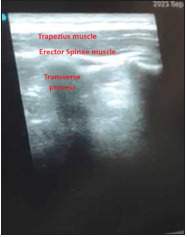

Methods: One hundred patients aged 4-12 years were randomly assigned into two groups, both groups received general anesthesia followed by bilateral sham erector spinae plane block at the level of T6 transverse process using 0.4 ml/kg normal saline on each side in the control group (group C) or bilateral ultrasound-guided erector spinae plane block at the level of T6 transverse process using 0.4 ml/kg ropivacaine 0.2% with a maximum dose of 2 mg/kg mixed with adrenaline 2 mcg/ml in erector spinae plane block group (group E). The postoperative pain scores were evaluated immediately post-extubation, at 1 hour, 2, 4, 6, 8, 10, 12, 14, 16, 18, 20, 22, and 24 hours after extubation, total consumption of intraoperative fentanyl and time to first rescue analgesic administration were also recorded.